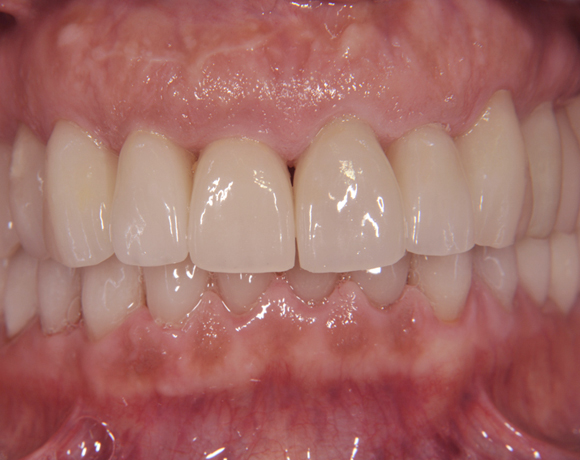

Der vorliegende Patientenfall zeigt eine komplette Neuversorgung der vorhandenen Metallkeramikkronen mit vollkeramischen Restaurationen. Zusätzlich wurde im Oberkiefer die Zahnreihe mit zwei Implantaten, für die fehlenden Molaren, ergänzt. Da keine ausreichende Knochenhöhe vorhanden war wurde ein interner Sinuslift geplant.